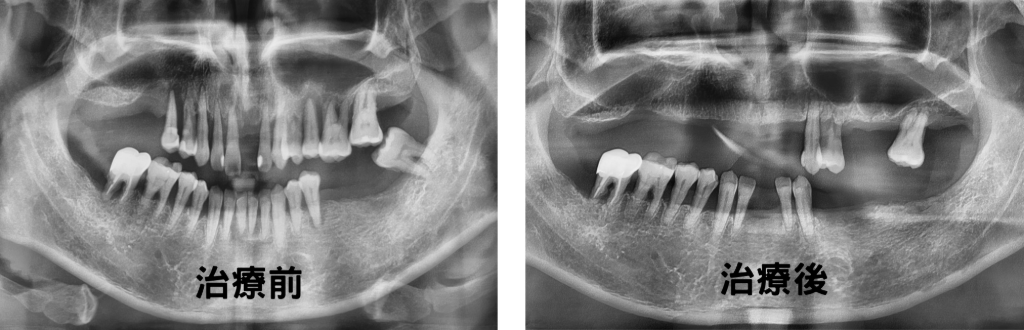

曾有一位5旬男性患者,早年因忙碌忽視牙周病,直到五年前牙齦出現腫脹疼痛以及陸續掉牙造成咀嚼困難才來求診。經吳醫師以牙周探針及X光檢查,發現牙牙齒動搖度高達2-3級,因此懷疑患者代謝系統異常,轉診後驚覺其飯後血糖竟高達410 mg/dL(正常飯後< 200 mg/dL),顯示胰島素功能失調。

▲ 曾有一位5旬男性患者,早年因忙碌忽視牙周病,直到五年前牙齦出現腫脹疼痛以及陸續掉牙造成咀嚼困難才來求診。(圖:聯新國際醫院)

吳醫師指出,血糖控制不佳會使牙周病機率提升2至3倍,若加上有抽菸習慣,風險將飆升至4.6倍。該患者在同步接受糖尿病與牙周病治療後,順利保住 11 顆牙並於牙周病療程結束後,進行假牙重建恢復正常咀嚼功能。同時患者亦遵從支持性療法定期回診,歷經五年追蹤,糖化血色素控制在7%以下,11顆牙也狀況良好,印證及早面對,積極治療的重要性。